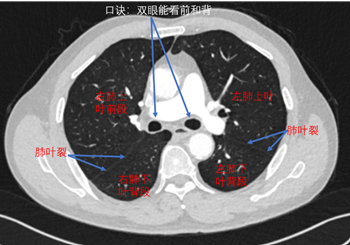

难者不会会者不难之「庖丁解肺」丨一页手册·协和八

看见左右主支气管(双眼)层面:右肺上叶前段和右肺下叶背段,左肺上叶和

右上叶支气管的前面的分支,就是右肺上叶前段支气管;后面的分支,就是